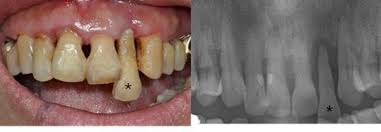

| 치근단농양 | 심한 통증, 고름 형성 | 근관치료(신경치료), 발치 필요할 수 있음 |